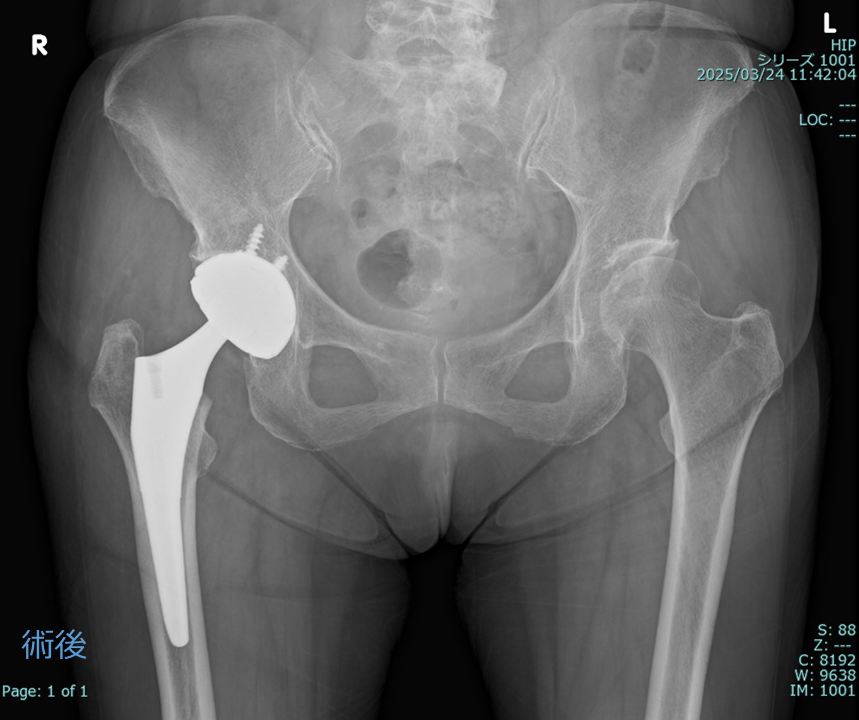

A)変形性股関節症、大腿骨頭壊死症や関節リウマチなどで股関節の軟骨が傷ついたり、すり減ったりして、痛みによって日常生活が障害される場合に人工股関節置換術を行います。大腿骨頭を切除し、骨に人工の部品(骨盤側にカップ、大腿骨にステム)を設置する方法で、ひどい虫歯を抜いてインプラントに入れ替えることに似たような考えです。

術後脱臼の予防や長期の耐久性のために人工関節のカップの設置角度には正確性が求められますので、ナビゲーションを用いたり、手術中にレントゲンで確認したり、より精度の高い手術を心がけています。